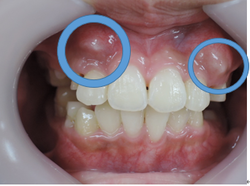

初診時

治療1年6カ月後

このように、1年6ヶ月間、通院して頂ければ治療計画どうりの目標は達成されます。

しかし、上下の顎骨の状態が改善されたからと言って永久歯が綺麗に並ぶわけではありません。

○印の中にある突起は永久歯の犬歯です。

但し、本来顎骨が劣成長であった場合はその中にある永久歯は著しい位置異常を起こしている場合が多い為に上下顎骨の大きさや咬み合わせの高さが改善したとしても、歯並びが悪くなる事がほとんどです。

その場合は永久歯の歯列矯正の計画の契約を結び永久歯の綺麗な歯並びと咬み合わせに改善していきます。